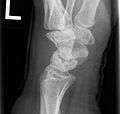

Left hand x-ray with Kienbock's Disease- Left hand x-ray post proximal row carpectomy